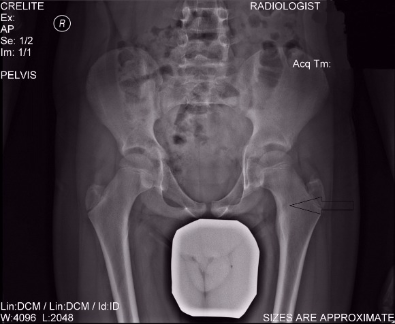

Η ακτινογραφία απεικονίζει ένα οστεοειδές οστέωμα στο άνω μέρος του μηριαίου, το οποίο θεραπεύτηκε από τον Δρ. Ζένιο, με την χρήση καυτηριασμού με ραδιοσυχνότητες.